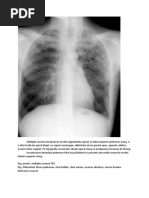

- prin calcul: CPT = CV + VR sau CPT = CI + CRF ; - prin metoda dilutiei He prin respiratie unica in circuit deschis - prin metoda radiologica: masurarea CPT pe radiografii toracopulmonare, efectuate in proiectii postero- anterioara si laterala, cu subiectul in apnee dupa un inspir maximal, eventual prelucrarea computerizata a rezultatului.